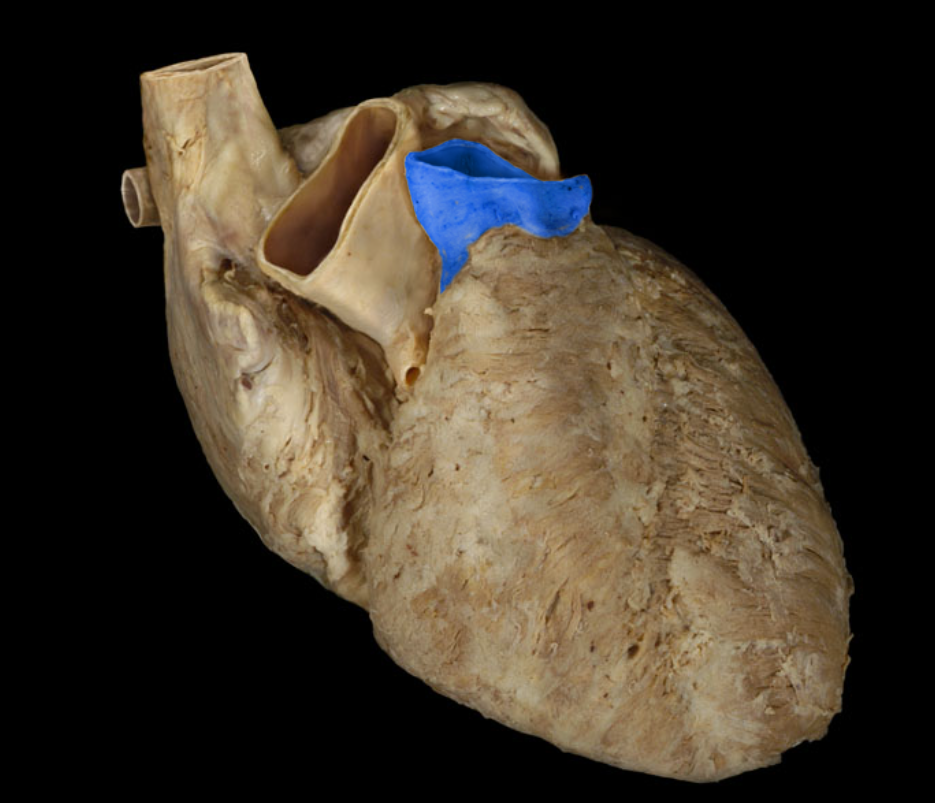

Left auricle